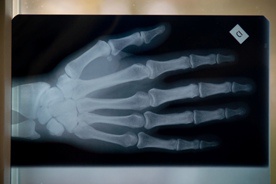

Dostał nową rękę

Replantacji całej kończyny dokonano po raz pierwszy w Polce w szpitalu Świętej Jadwigi w Trzebnicy. 30-letniemu mężczyźnie przeszczepiono prawą rękę na wysokości połowy ramienia od zmarłego dawcy. Pacjent czuje się dobrze, teraz czeka go długa rehabilitacja.

Jak powiedział w środę PAP ordynator oddziału replantacji kończyn trzebnickiego szpital doc. Jerzy Jabłecki, to pierwsza w Polsce tego typu transplantacja i trzecia w świecie. Pacjent, któremu przeszczepiono rękę stracił ją 28 lat temu. "Nigdzie na świecie nie dokonano replantacji ręki po tak długim okresie" - zwrócił uwagę docent.